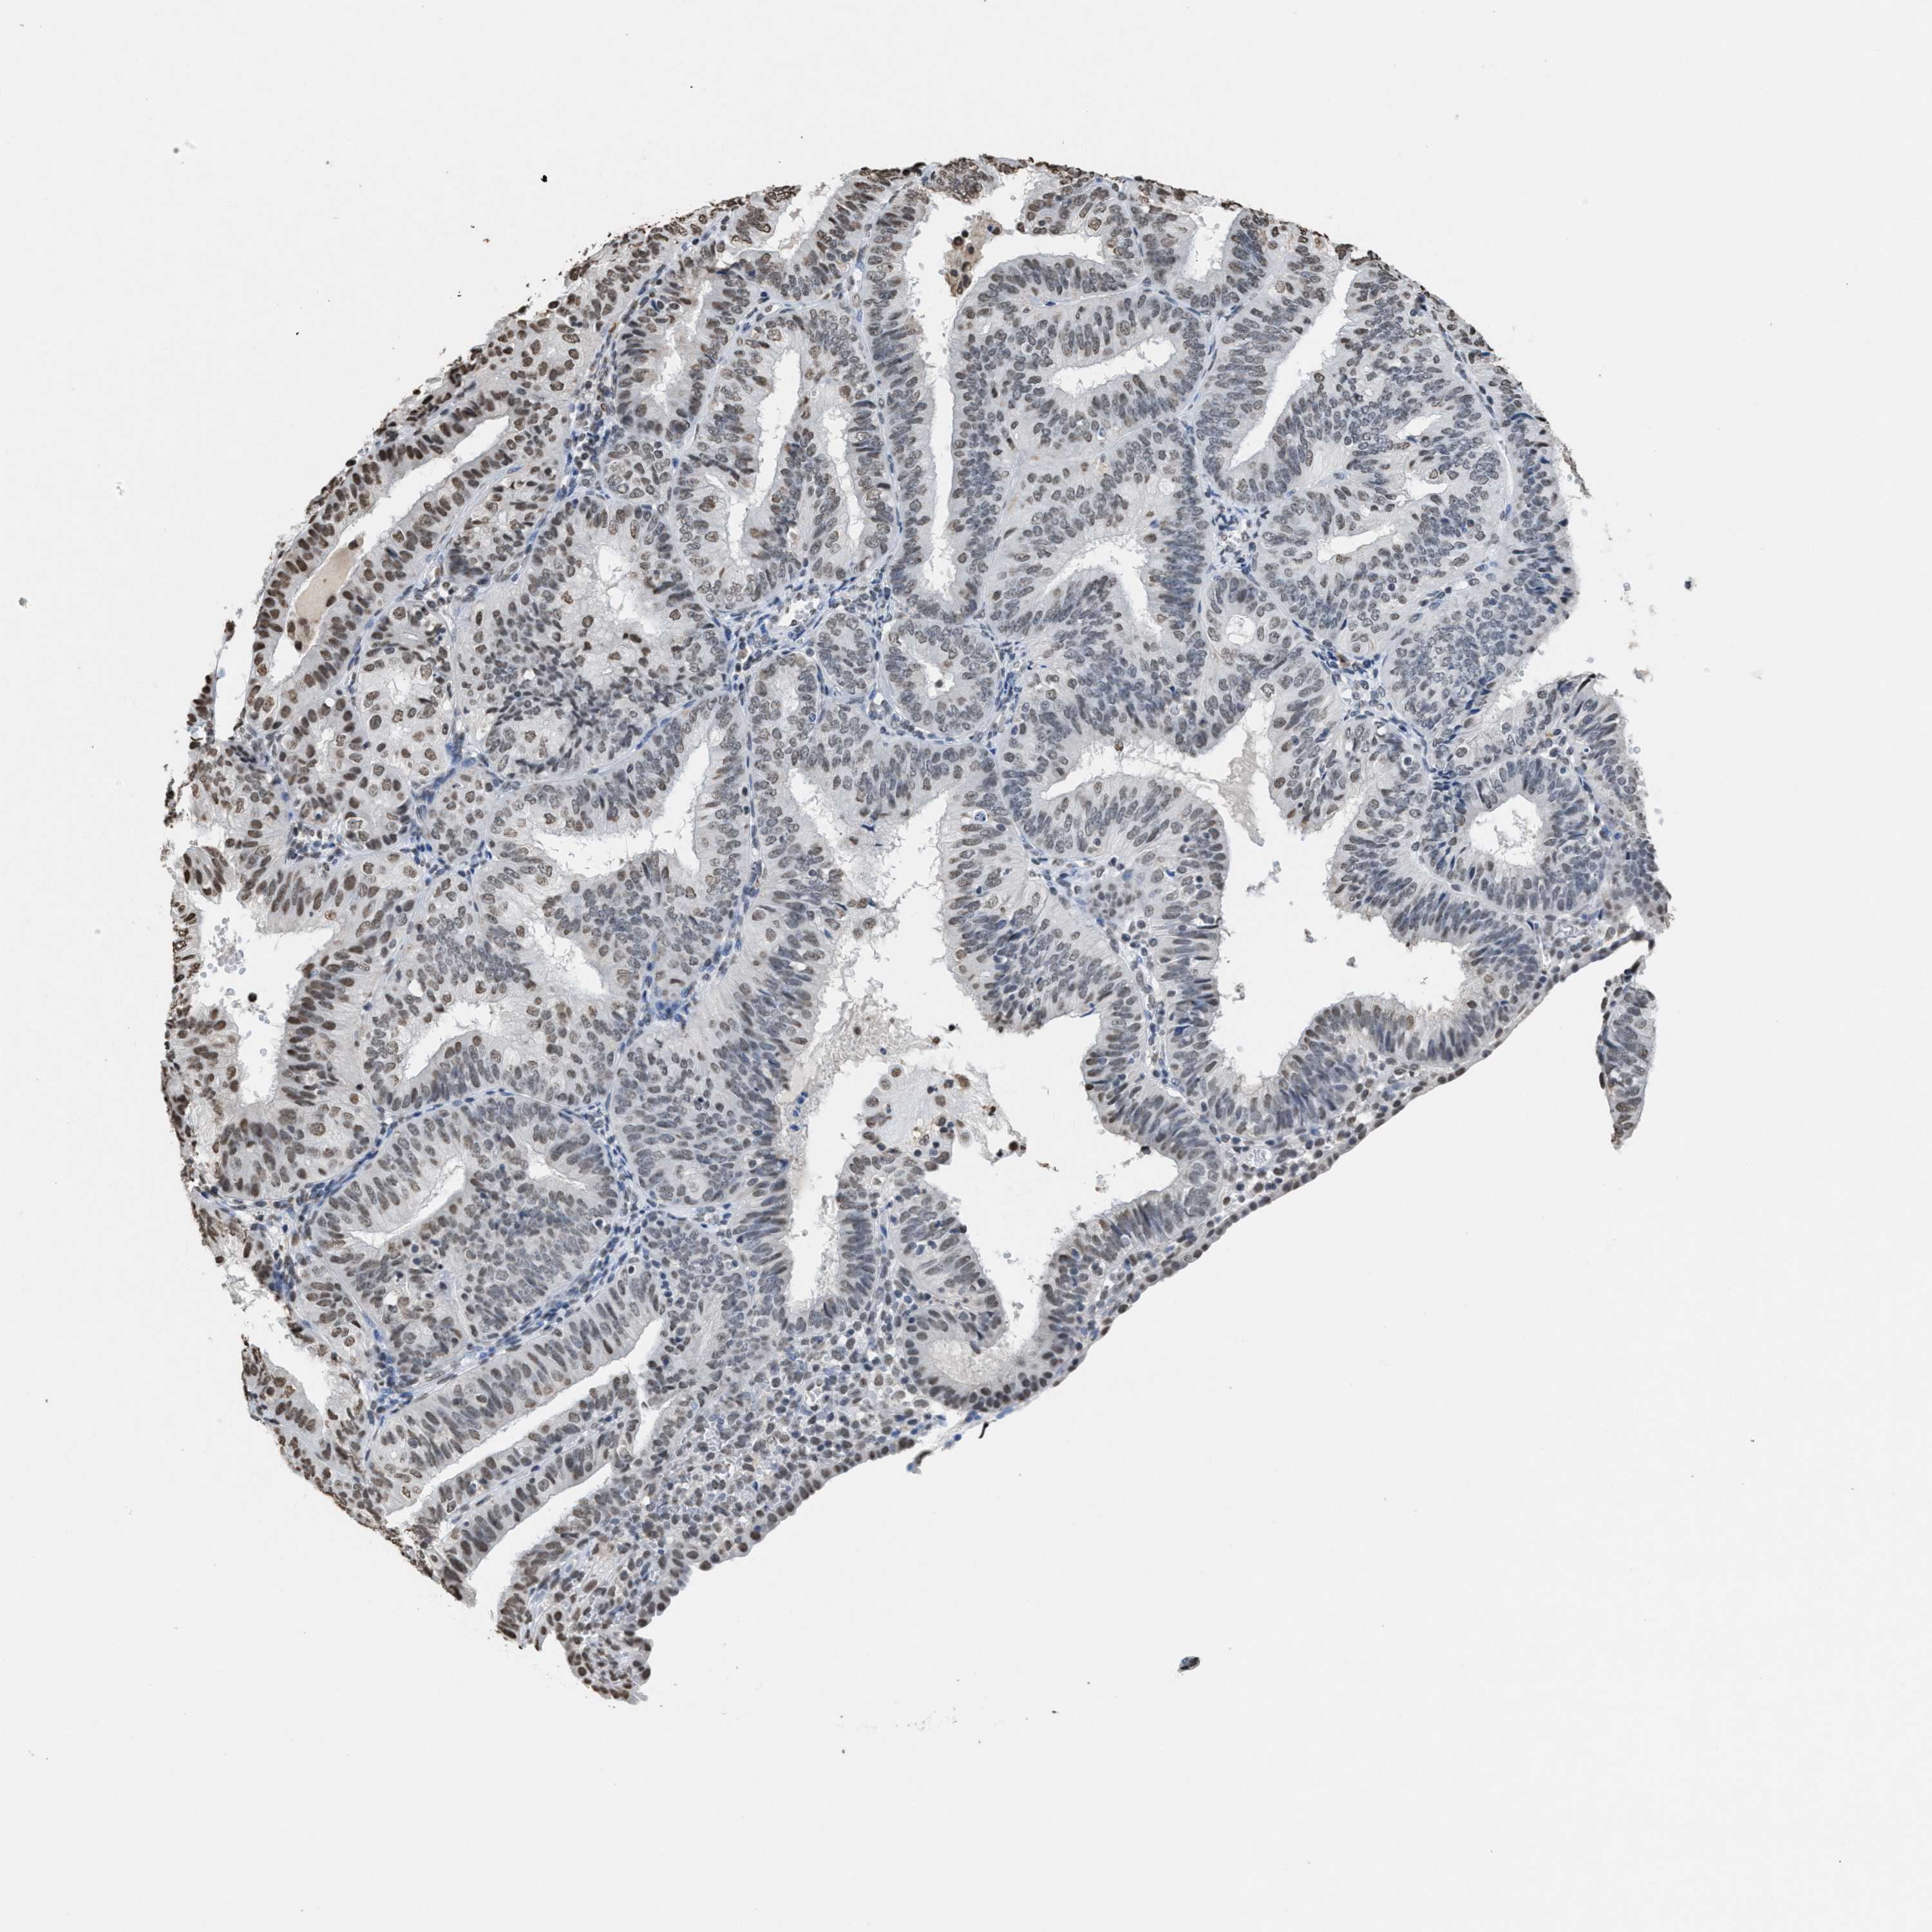

ENDOMETRIAL CANCER - Protein expressioni

A mouse-over function shows sample information and annotation data. Click on an image to view it in a full screen mode. Samples can be filtered based on level of antibody staining by selecting one or several of the following categories: high, medium, low and not detected. The assay and annotation is described here.

Note that samples used for immunohistochemistry by the Human Protein Atlas do not correspond to samples in the TCGA dataset.

Antibody stainingi

Antibody staining in the annotated cell types in the current human tissue is reported as not detected, low, medium, or high, based on conventional immunohistochemistry profiling in selected tissues. This score is based on the combination of the staining intensity and fraction of stained cells.

Each image is clickable and will lead to virtual microscopy that enables deeper exploration of all samples and also displays staining intensity scores, fraction scores and subcellular localization as well as patient and tissue information for each sample.

Antibody HPA021816

Antibody CAB002209

Staining

High

Medium

Low

Not detected

Intensity

Strong

Moderate

Weak

Negative

Quantity

>75%

75%-25%

<25%

None

Location

Nuclear

Cytoplasmic/membranous

Cytoplasmic/membranous,nuclear

Adenocarcinoma, NOS

Adenoma, NOS

Neoplasm, malignant, NOS